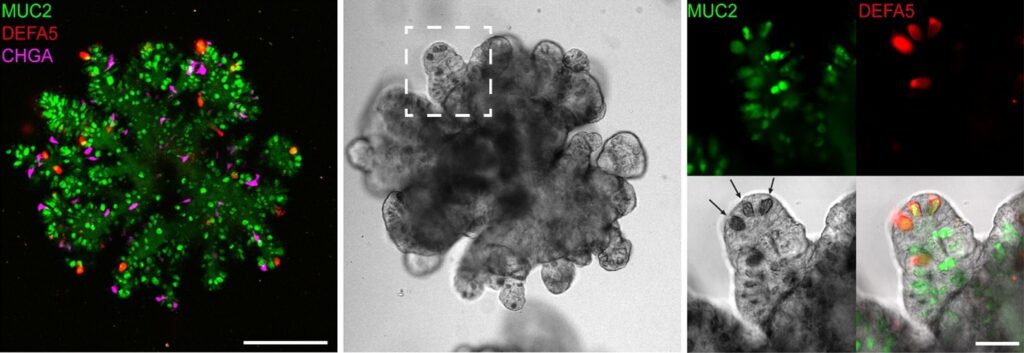

The Gut-on-a-Chip technology marries two revolutionary concepts: organoids and microfluidic devices. Organoids are miniature, 3D tissue structures derived from stem cells that replicate the structure and function of specific organs. Microfluidics, on the other hand, involves the manipulation of small fluid volumes within microscale channels. Scientists have created a platform that mimics the physiological and mechanical aspects of the human gut more accurately than traditional cell culture methods (2).